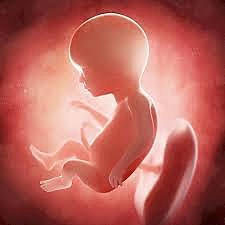

El bebé mide entre 11 y 13 centímetros y pesa unos 100 gr. Su aspecto se va pareciendo cada vez más al de un recién nacido. La grasa empieza a aparecer en todo su cuerpo es importante para mantener el calor corporal y regular del metabolismo del organismo. El agua forma parte de la tercera parte del cuerpo del feto en esta etapa del desarrollo. La posición habitual es semiflexionada con las manos a la altura de la barbilla y los pies cruzados por debajo de la salida del cordón umbilical.

El bebé mide entre 12,5 y 14 centímetros y pesa unos 150 gramos. Parte de la sangre de la aurícula derecha pasa directamente a la aurícula izquierda a través de un agujero llamado foramen oval, evitando así el paso de esa sangre por los pulmones. En el momento del nacimiento, este agujero se cierra. Los pies y las piernas están moldeados. Es decir, las porciones cartilaginosas que hasta el momento han formado el esqueleto del feto, se transforman en tejido óseo.

Durante estos días, el cuerpo del bebé sufre muchos cambios (a mejor) y tú también notas transformaciones físicas, como cambios genitales o palpitaciones. El sistema nervioso del feto, formado por el cerebro y la médula espinal, sigue desarrollándose. En cuanto a la forma del cuerpo, la parte inferior de tu bebé es todavía delgada y estrecha en comparación con la cabeza y el torso. Los genitales aparecen engrosados al visualizarlos en ecografía.

Tu bebé mide entre 14 y 16 cm y pesa 260 gra la piel que cubre el cuerpo de tu hijo se desarrolla a través de dos capas: la epidermis, más superficial, y la dermis, situada por debajo de la anterior empiezan a aparecer las arrugas en las palmas,pies que darán lugar a los patrones característicos de cada ser humana las glándulas de la piel fetal segregan una sustancia blanquecina y pastosa llamada vérnix caseosa. Esta sustancia protege la piel del feto contra la agresión del líquido amniótico.

el crecimiento del útero ya es evidente. La musculatura abdominal de la madre se adapta al bebé que se desarrolla en su interior. El pequeño se sigue moviendo a sus anchas y absorbe nutrientes del líquido amniótico que le rodea.